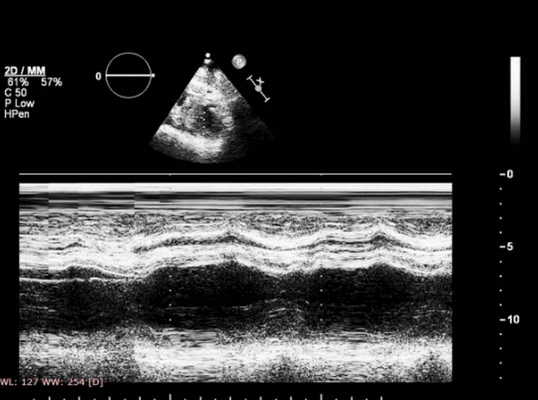

3. Систолическое смещение трикуспидального кольца (ССТК) (Tricuspid annular plane systolic excursion - TAPSE): показано, что это хороший показатель для оценки продольной функции ПЖ и показывает степень систолического движения латеральной части трехстворчатого кольца к верхушке [2].. Его можно легко определять при апикальном четырехкамерном сечении, используя двухмерный или М-режимы. При М-режиме курсор направляется от верхушки к латеральной части трикуспидального кольца. В норме его смещение в сторону верхушки превышает 2 см [17]. По рекомендациям ASE ССТК < 16мм ассоцируется с систолической дисфукцией ПЖ [8]. При остром ИМ ПЖ оно снижается и может служить маркером плохого прогноза [18, 19]. По нашим данным ССТК ≤ 14мм при остром ИМ ЛЖ нижней локализации ассоцируется с увеличением госпитальной смертности [20]. ССТК - простой при применении метод, но он имеет свои ограничения: оценка ограничена продольной функцией свободной стенки ПЖ, не учитывая вклад межжелудочковой перегородки и выхосящего тракта ПЖ [21]. ASE рекомендует применять ССТК рутинно как простой метод оценки функции ПЖ.